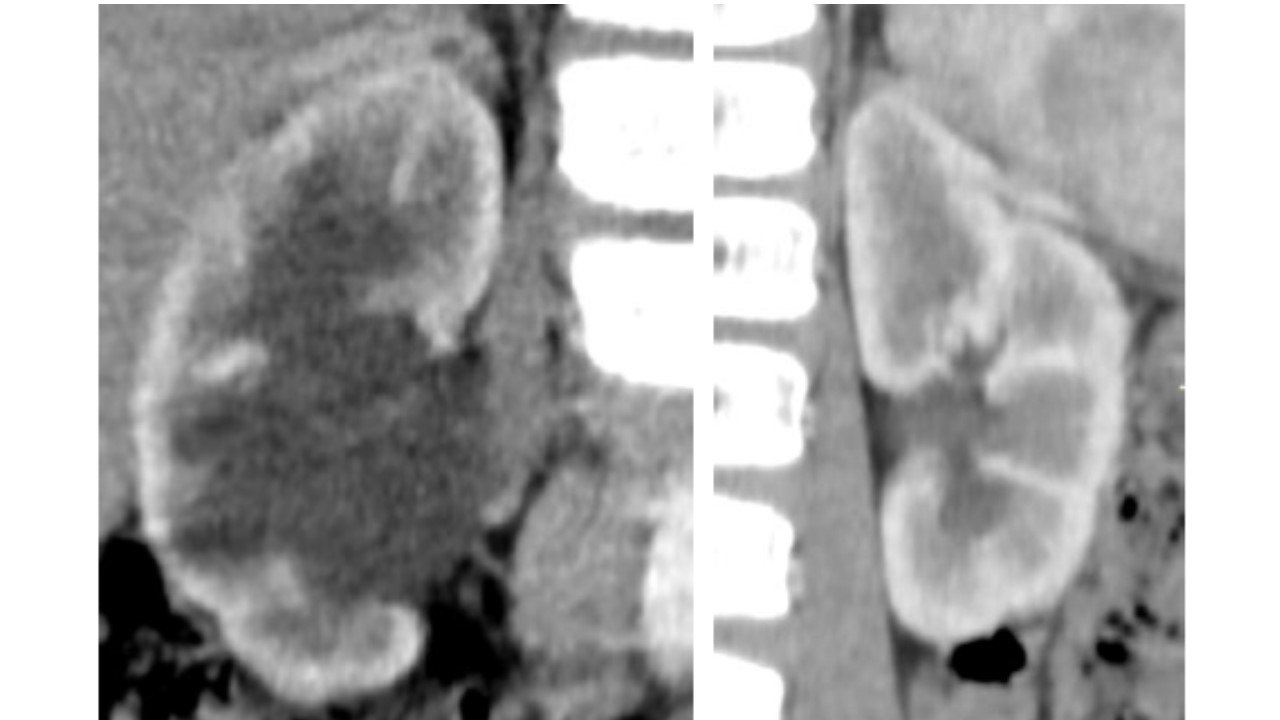

Imagem 10

ESTENOSE DE JUP, NEM SEMPRE IDIOPÁTICA

10/08/2020 14:50

Ler Mais